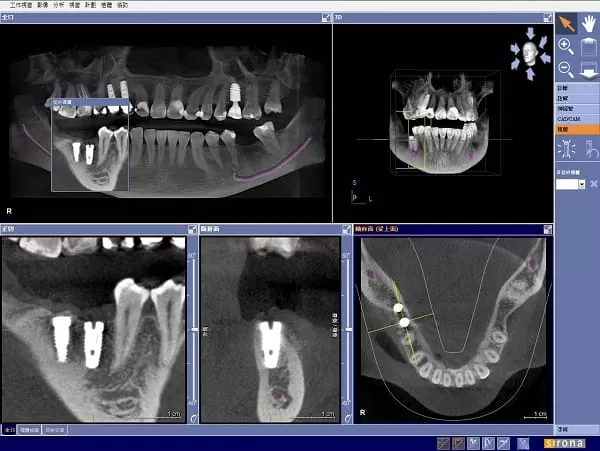

(圖1) 傳統平面X光片無法顯示立體的影像

隨著國人口腔衛生意識抬頭及國外人工植牙的成功與進步,近年來台灣接受人工愈多,但傳統平面X光片無法顯示立體的影像(圖1),不足以精準判斷缺牙位置的骨質寬度及密度,所以植牙前皆需拍攝電腦斷層( Computerized Tomography,簡稱CT),CT讓醫師能準確判斷及評估,是牙科極具代表性,卻也是相當昂貴的設備之一,目前也不是每家診所都能有此項設備。

(圖2)橘色虛線為模擬放入植體的適當位置

對於植牙醫師而言,CT的便利性,即是具有模擬植體植入的功能(圖2)。因為每位患者的顎骨結構不同,為了因應病人口腔現況及符合牙齒對應的咬合功能,植牙醫師需考量在術前判斷植體植入的位置是否恰當,由於CT所拍攝出來的影像是立體的,可以360度旋轉(圖3),可進一步判斷齒槽骨的骨質及植體植入的寬度與深度以避免植牙常見的問題案例:上排植體穿過鼻腔造成鼻竇破裂或是下排植體不小心碰到齒槽骨神經,可能造成半邊臉麻痺等問題發生(圖4)。所以進行拍攝「口腔電腦斷層CT」也是對患者進行植牙手術的安全與保障。

(圖3) 3D立體影像清楚呈現牙齒與口腔狀況

(圖4) 3D全口影像,可清楚呈現下顎神經管,紫線表示神經管

植牙前在「口腔狀況的判讀」是非常重要的,傳統平面全口X光片簡稱PANO,它們「只能顯現平面影像,無法展示口腔狀況的切面與橫斷面,容易造成骨質與骨量判讀上的誤差。CT則是呈現3D影像,並且有一個專屬的視窗(圖5),可以很清楚地往舌側的方向橫切過去,讓橫切面全部顯現出來。當醫師在與病人解說時,可以移動視窗顯示病人骨質的寬度及神經管的位置,另外可置入虛擬植體圖示(圖6),讓病人更清楚明白醫師的解說以及要為他植牙的位置及角度。

(圖5) CT呈現3D影像,醫師講解時可移動視窗顯示病人骨質的寬度及神經管的位置